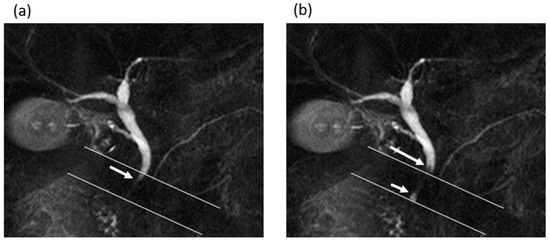

Figure 4.

A 75-year-old man in the gallstone group. (a,b) Cine-dynamic MRCP images with a spatially selective IR pulse. (a) The antegrade bile flow was shown as high signal intensity (arrow) within the area of the IR pulse, showing a grading score of 4. (b) The reverse bile flow was seen as low signal intensity outside the area of the IR pulse (long arrow) and was also observed as high signal intensity coming from duodenal papilla side into the area of the IR pulse (short arrow). The grading score of reverse bile flow was categorized as 2.

In comparing MRI measurements between the gallstone group and the non-gallstone group (Table 1), the diameter of the common bile duct was significantly larger in the gallstone group (7 (range, 6–8) mm) than in the non-gallstone group (6 (range, 5–7.5) mm) (p = 0.015). The frequency and mean secretion grade of the antegrade bile flow were significantly higher in the gallstone group than in the non-gallstone group (frequency, 8 times (range, 4–11) vs. 3 times (range, 0–8); mean secretion grade, 0.55 (range, 0.25–0.85) vs. 0.2 (range, 0–0.4)), while no significant differences in those values of the reverse bile flow were found between the groups (frequency, p = 0.729; mean secretion grade, p = 0.703) (Figure 3 and Figure 4).